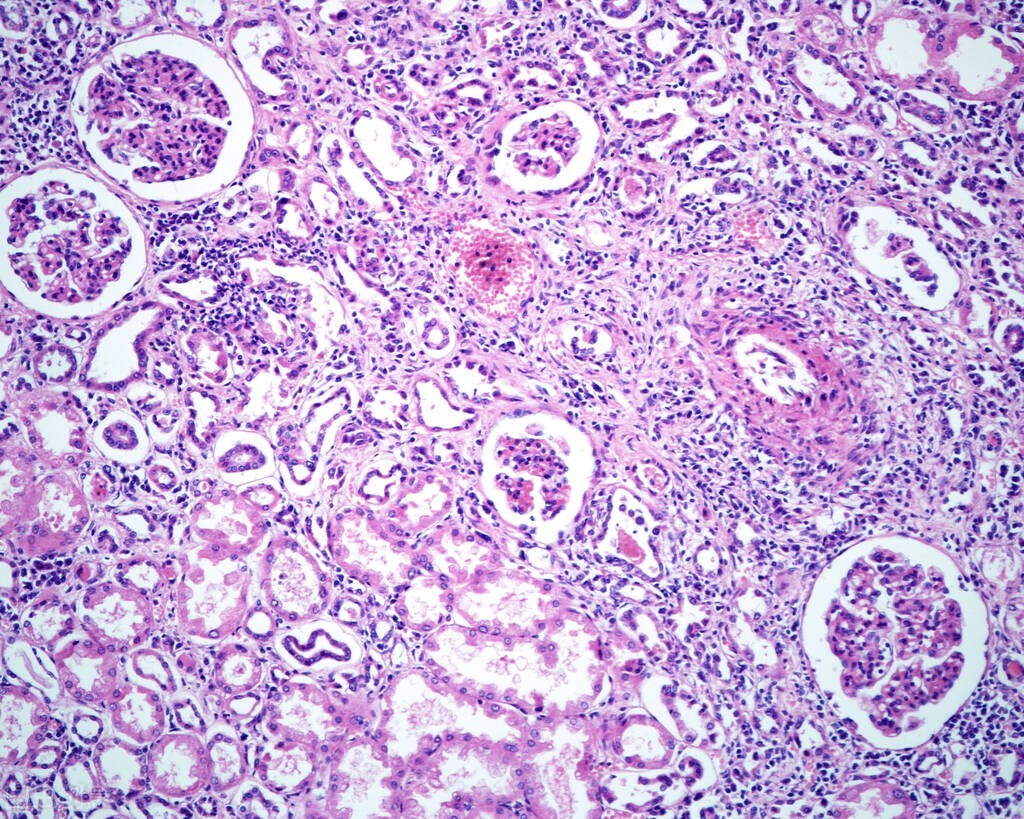

2、电镜检查

可发觉侵犯毛细血管后静脉,特别是侵犯8~30μm大小血管。初期为血管内皮细胞肿胀,内皮细胞间发生裂隙和吞噬细胞活跃状况,基底膜变厚。中性白细胞逐渐在血管的间质内。重则血小板凝聚于管腔内,并在内皮细胞间越过。